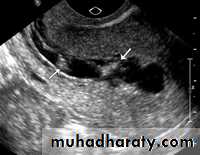

ULTRA SOUND ,MRI , and on menstrual history